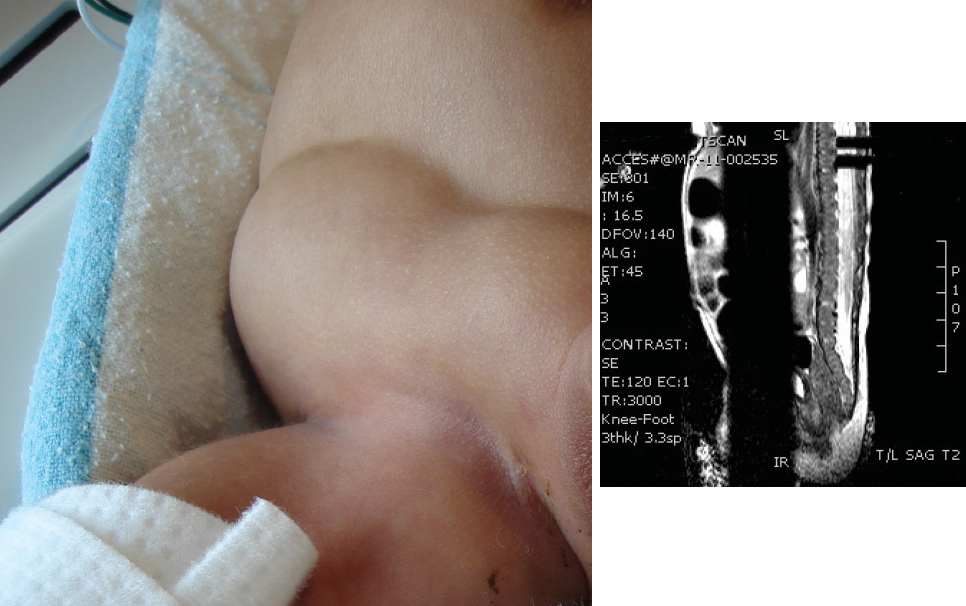

MRI of the spine showed a tethered spinal cord at the level of the 4th and 5th lumbar vertebrae and absent posterior elements of the lower sacrum (Figure 3). An echocardiogram showed mild left pulmonary stenosis.

Figure 3. MRI showed a low-lying spinal cord, absent posterior elements of the sacral vertebrae, and a tethered cord at the 4th and 5th lumbar vertebrae.